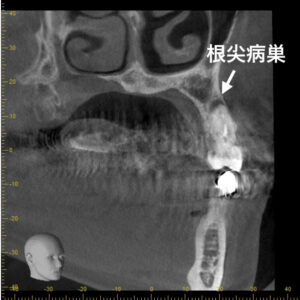

横から見た状態

奥歯3本の状態が悪いことが確認できました。

上記画像で根の先の黒く抜けている部分は元々骨のある部分が菌によって溶けてしまっている状態を示しています。